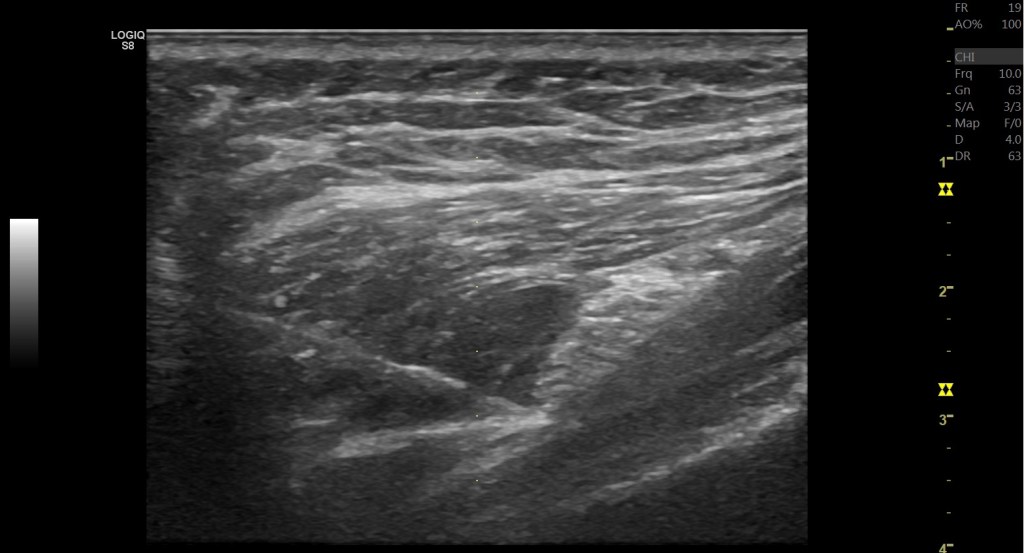

這些都可以在動態超音波底下去區分壓迫到的位置與原因。

可以看到在股骨內轉時,其實坐骨神經的張力是會增加的。因此在診斷梨狀肌壓迫坐骨神經前,完整的理學檢查其實還是非常重要,畢竟這些理學檢查都無法100%的診斷,需要結合2-3項理學檢查,甚至透過診斷性注射來確認壓迫的位置。